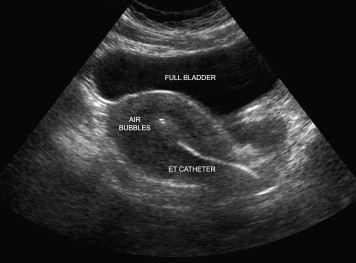

Embryo transfer

S.S.G(सोनोसालफिंगोग्राफी) गर्भाशयात विशिष्ट प्रकारचे औषध सोडून सोनोग्राफीच्या साहाय्याने गर्भाशय व नळयाची तपासणी